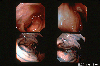

A case of endocrine-cell carcinoma showed a submucosal tumor like appearance in 1990's.

Endoscopy